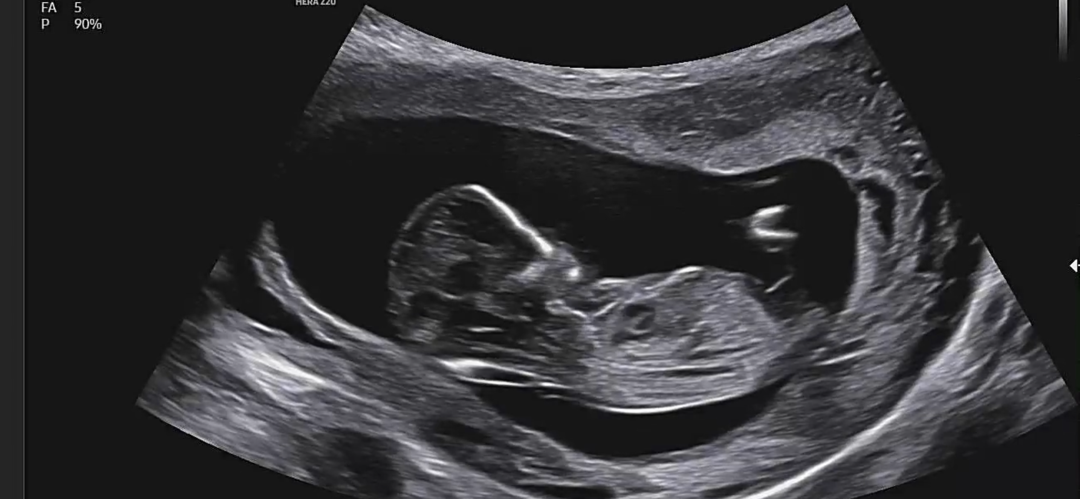

12주6일차 1차 기형아 검사 하고왔어요

둘찌 임신중이에요 첫째가 딸이라 아들이면 좀 더 좋을것같다고 생각하는중인데 어때보이시나요~?